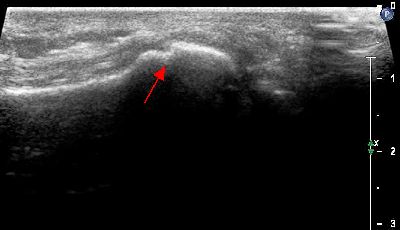

Becco osteofitico falange prossimale becco osteofitico falange prossimale